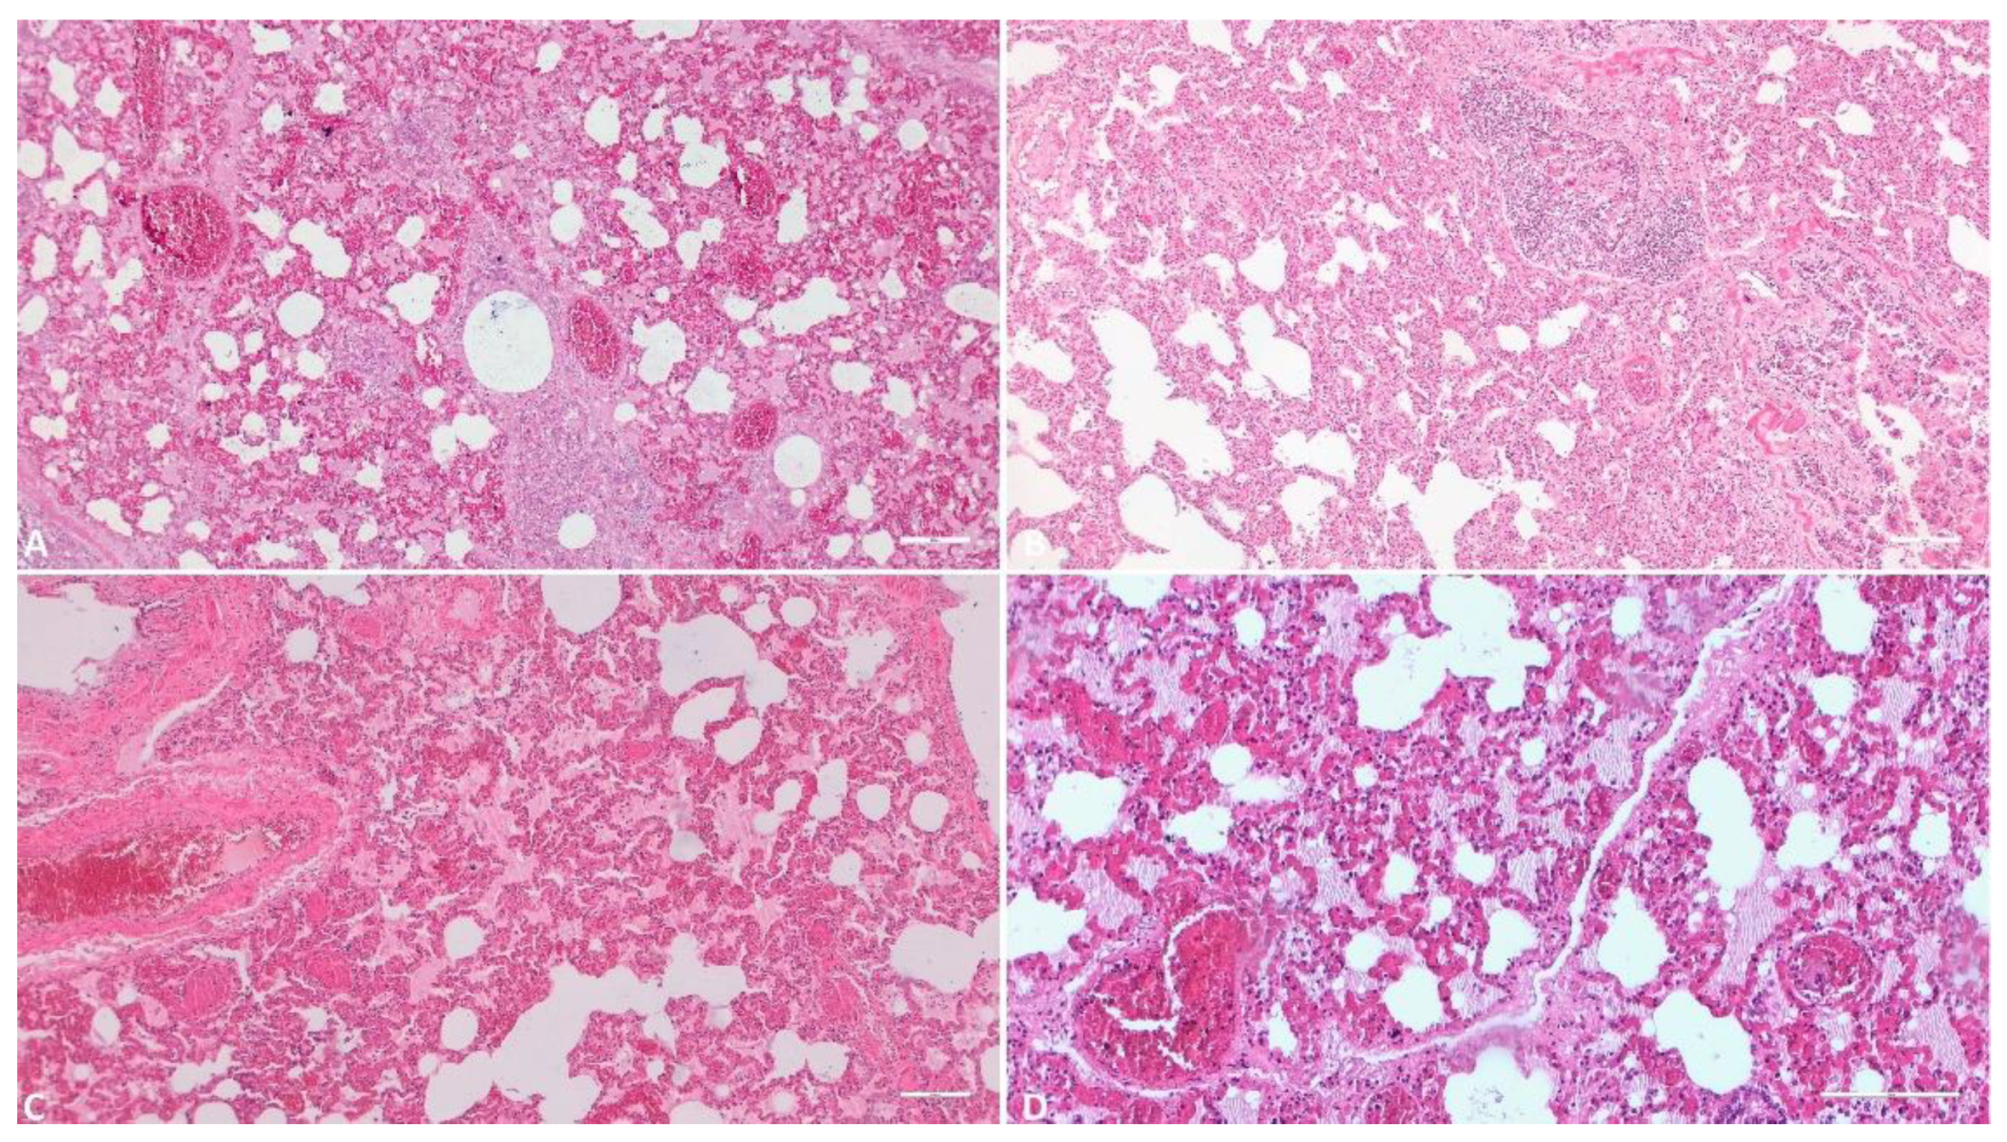

3.1.1. Kidney

3.1.2. Liver

3.1.3. Gallbladder

3.1.4. Spleen

3.1.5. Lymph Node

3.1.6. Heart

3.1.7. Lung

3.1.8. Tonsil